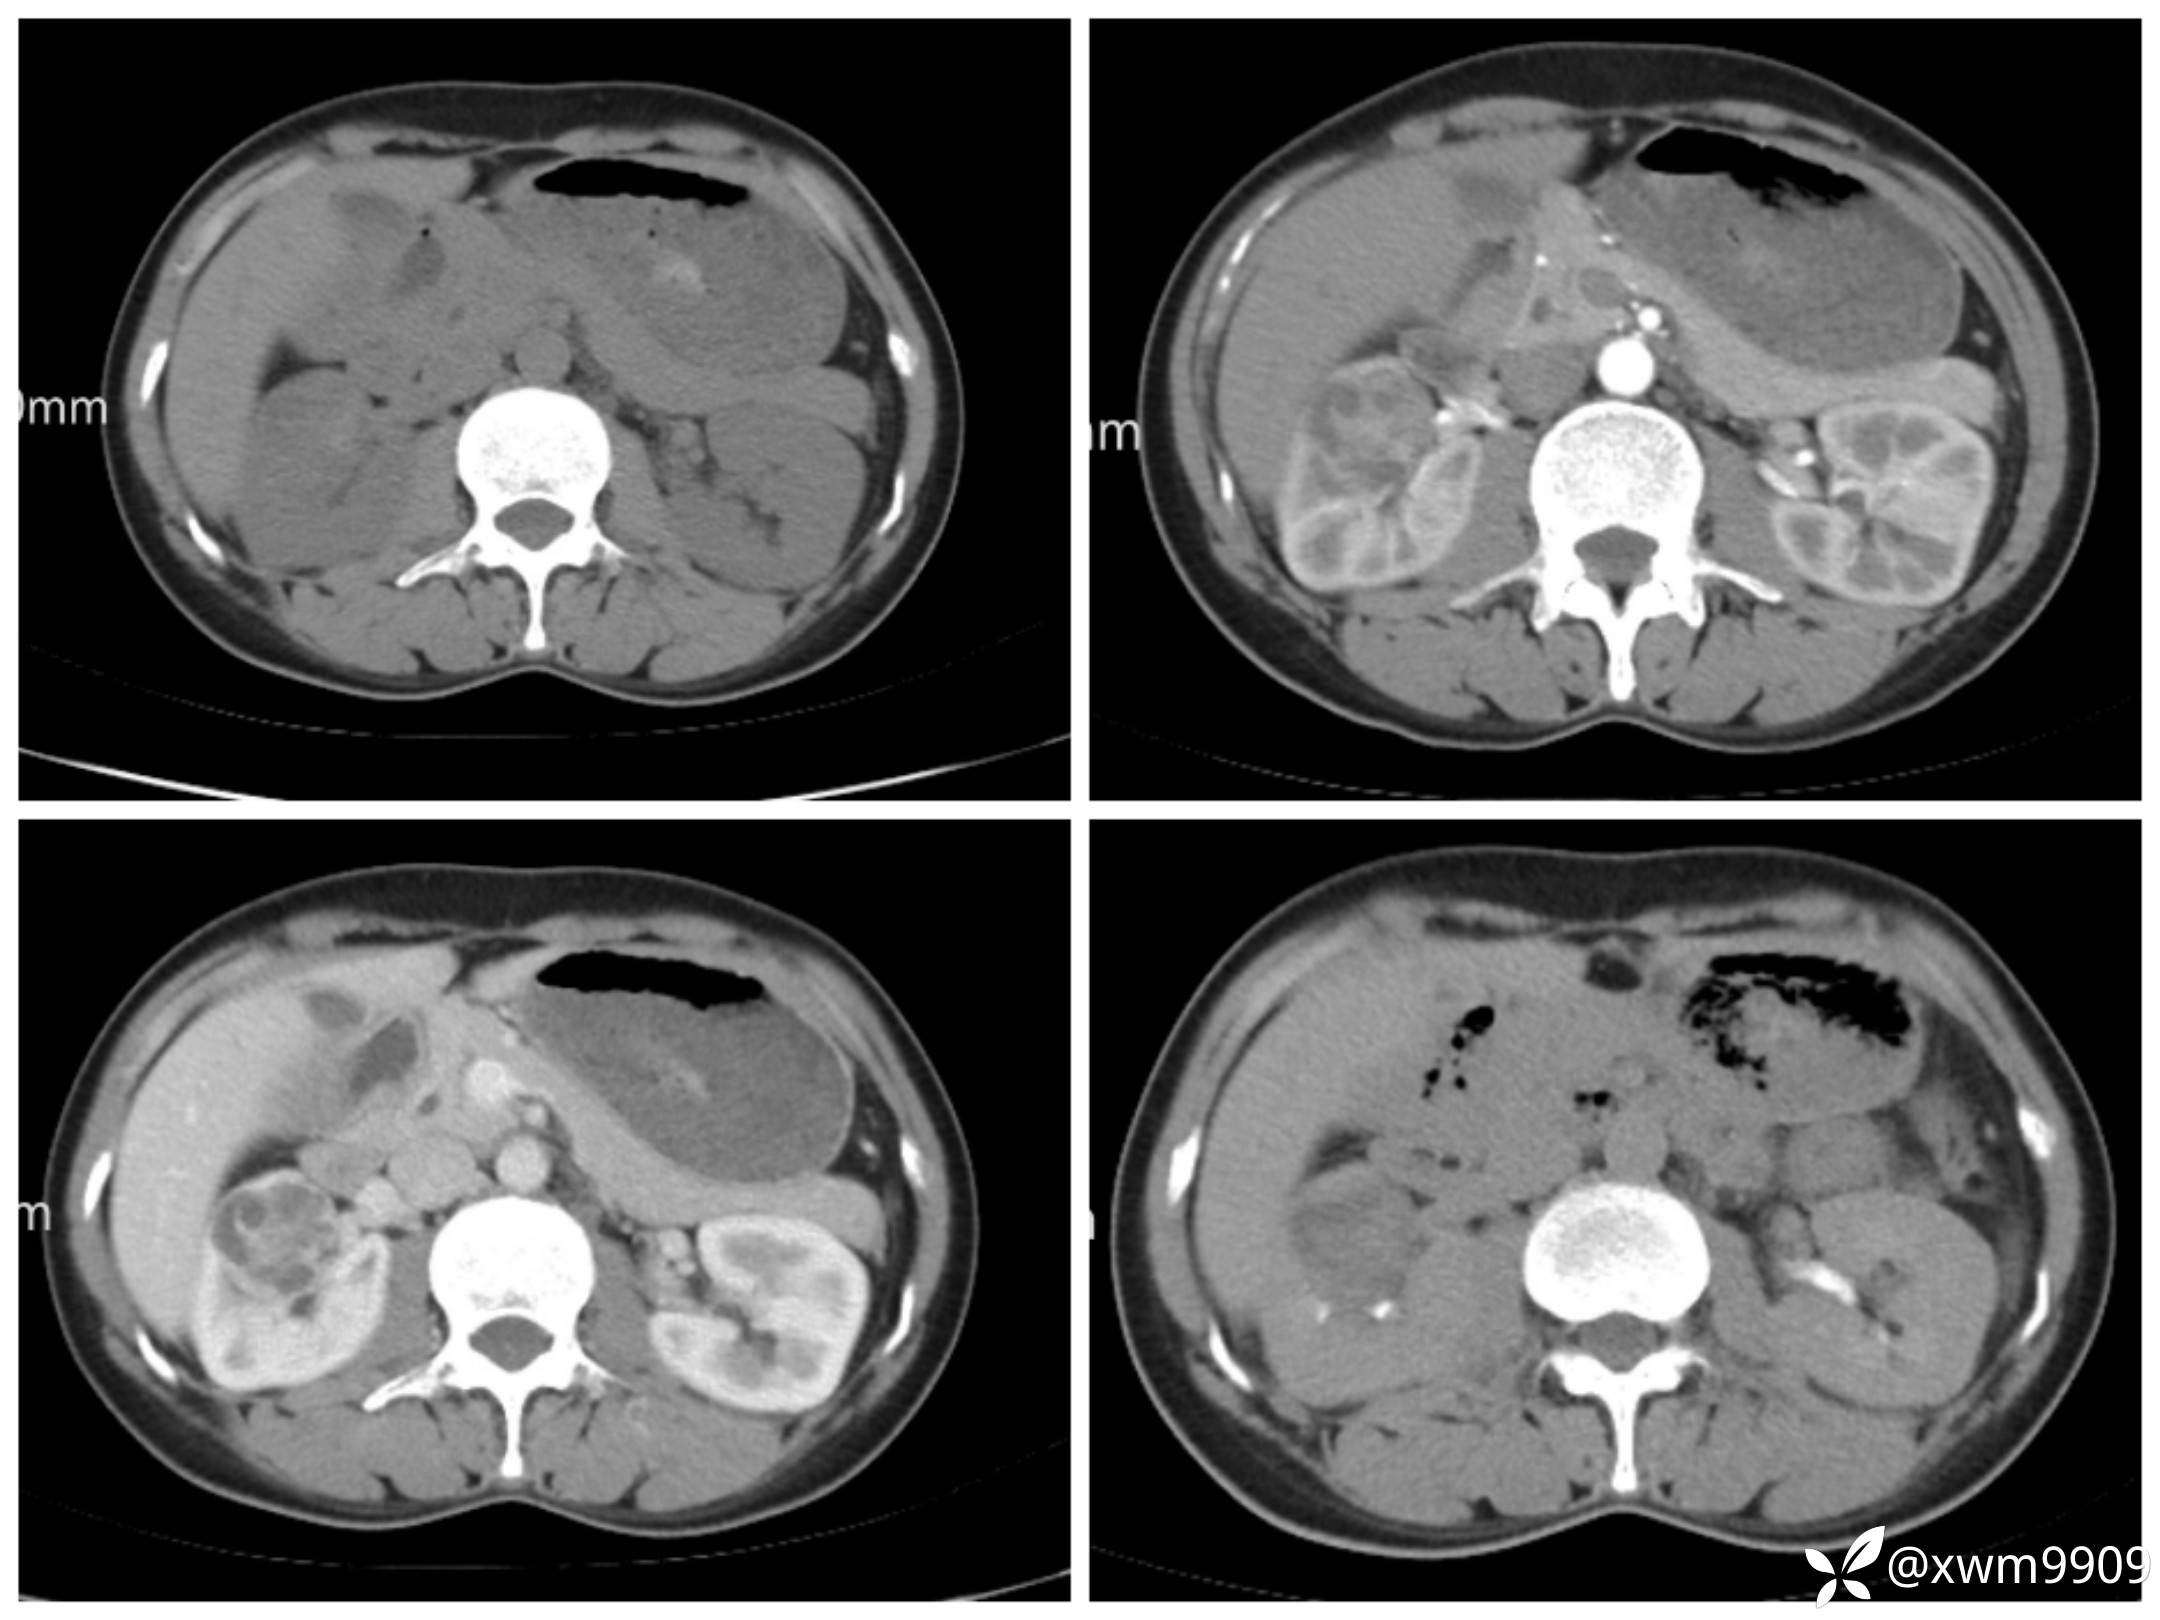

T2:

反相位:

同相位:

LAvA:

A:

v:

平衡期:

DwI丶ADC: